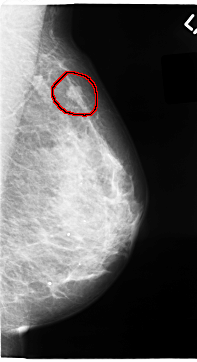

C_0065_1.LEFT_MLO

LEFT_MLO LINES 4704 PIXELS_PER_LINE 2552 BITS_PER_PIXEL 12 RESOLUTION 50 OVERLAY

FILE: C_0065_1.LEFT_MLO.OVERLAY

TOTAL_ABNORMALITIES 1

ABNORMALITY 1

LESION_TYPE MASS SHAPE LOBULATED MARGINS MICROLOBULATED

ASSESSMENT 4

SUBTLETY 5

PATHOLOGY MALIGNANT

TOTAL_OUTLINES 1

BOUNDARY